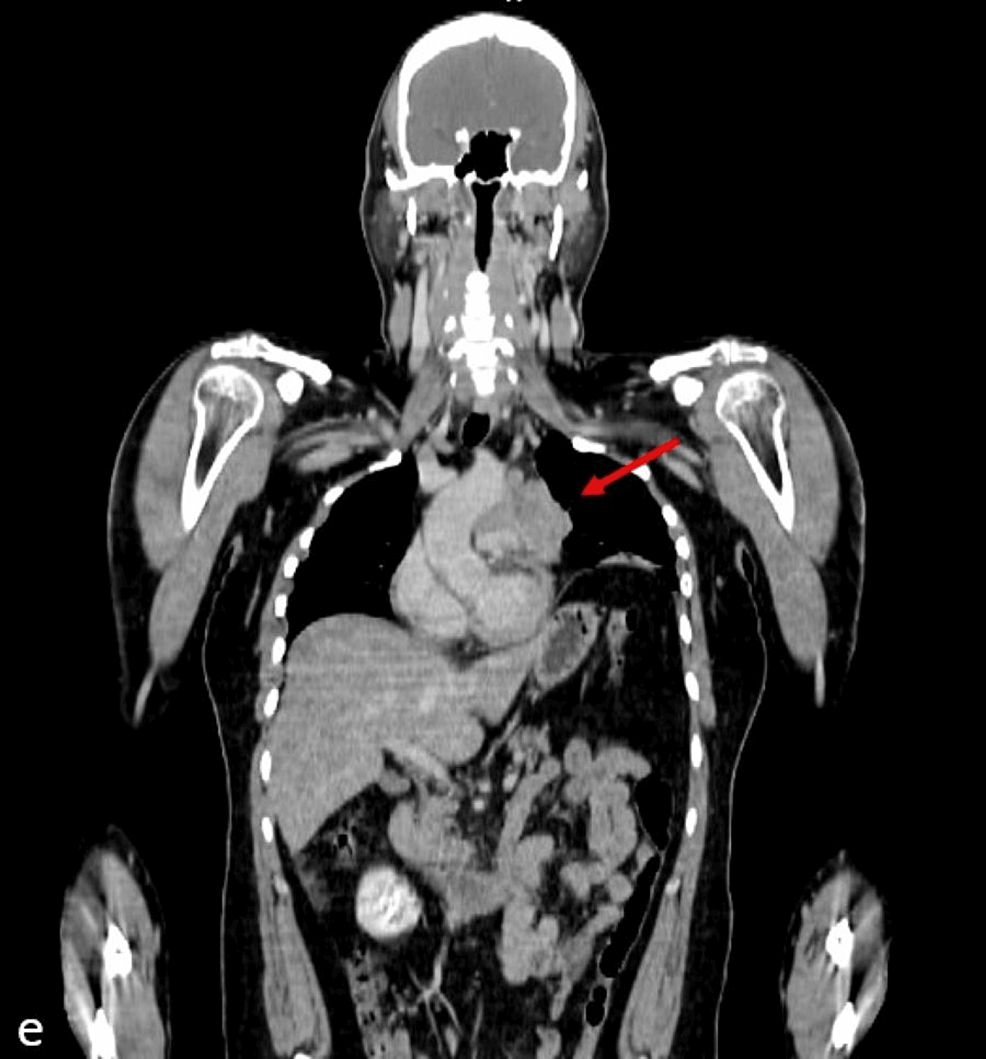

Cancers Free FullText Thymic Lymphoepithelial Carcinoma Associated Thymic Lymphoepithelial Carcinoma Thymic lymphoepithelial carcinoma (tlec) is a primary thymic carcinoma that accounts for about 14% of all thymic epithelial tumors and is classified into. In the who 2021 classification, thymic carcinoma includes the following new subtypes (): Thymic epithelial tumors (tets) are rare tumors, including thymoma, thymic carcinoma, and thymic neuroendocrine tumors. (1) micronodular thymic carcinoma with lymphoid hyperplasia (fig. The. Thymic Lymphoepithelial Carcinoma.

Figure 1 from Thymic Lymphoepithelial Carcinoma Associated with Epstein Thymic Lymphoepithelial Carcinoma (1) micronodular thymic carcinoma with lymphoid hyperplasia (fig. Thymic lymphoepithelial carcinoma (tlec) is a primary thymic carcinoma that accounts for about 14% of all thymic epithelial. Thymic epithelial tumors (tets) are rare tumors, including thymoma, thymic carcinoma, and thymic neuroendocrine tumors. In the who 2021 classification, thymic carcinoma includes the following new subtypes (): The recognition of clinical, radiologic, and.. Thymic Lymphoepithelial Carcinoma.

Cancers Free FullText Thymic Lymphoepithelial Carcinoma Associated Thymic Lymphoepithelial Carcinoma The recognition of clinical, radiologic, and. In the who 2021 classification, thymic carcinoma includes the following new subtypes (): Thymic lymphoepithelial carcinoma (tlec) is a primary thymic carcinoma that accounts for about 14% of all thymic epithelial tumors and is classified into. (1) micronodular thymic carcinoma with lymphoid hyperplasia (fig. Thymic lymphoepithelial carcinoma (tlec) is a primary thymic carcinoma that. Thymic Lymphoepithelial Carcinoma.